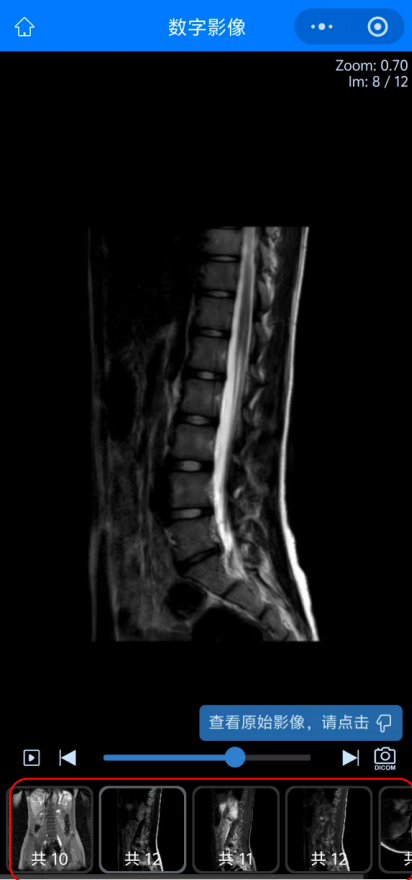

05 而點擊“查看影像”后查看到的患者的影像圖像,可以選擇下方紅色方框內(nèi)不同影像檢查或圖象處理方法來查看不同影像圖像。

09 如何進行圖像下載:首先在查看圖像功能內(nèi)點擊右下方照相機圖標(biāo),進入“查看原始影像”。